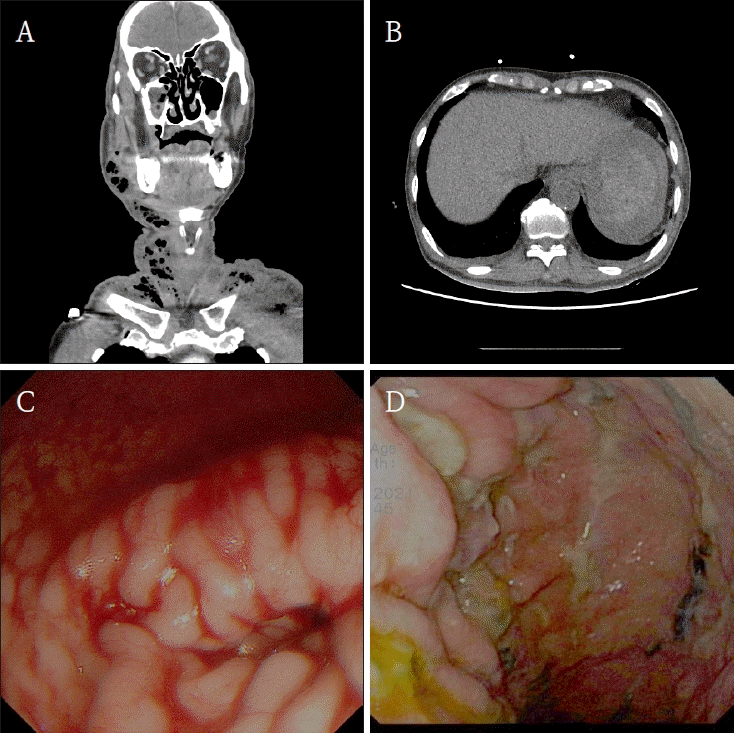

An 80-year-old man was admitted to emergency center, with complaints of swelling extending from the right mandible to the neck. He also complained of chest pain. These symptoms developed a week after the extraction at a local dental clinic. He had medical history of hypertension.The patient was alert but showed hypotension (99/49 mmHg) and hematemesis. Initial laboratory tests showed an RBC count of 1.64 × 10⁶ /μL, and a Hb level of 5.1 g/dL. Fluid resuscitation and blood transfusions were initiated. Neck CT showed an abscess extending from the right mandible to the deep neck space and mediastinum (Fig. 2A). Abdomen CT further indicated possible hematoma formation in stomach (Fig. 2B). A medication history found that he had taken additional painkillers with the prescribed analgesics to relieve the pain.An emergency upper gastrointestinal endoscopy was performed. However, visualization was limited by a large amount of intragastric hemorrhage and the patient's poor cooperation. Continuous PPI therapy with 2 vials of esomeprazole (OMPS injection 40 mg, Chong Kun Dang Pharmaceutical Corp., Seoul, Korea) mixed in 100 mL of normal saline was initiated, and the patient was kept NPO.On the second day of admission, due to hypovolemic shock and unstable vital signs, embolization of the left gastric artery was performed, and the patient was subsequently transferred to the intensive care unit (ICU). An active bleeding with multiple mucosal ulcerations was found in follow-up gastrointestinal endoscopy (Fig. 2C). Blood clots were removed, and hemostasis was achieved through epinephrine injection and cauterization.Surgical drainage for the abscess was delayed due to unstable systemic condition, including hypovolemic shock, acute kidney injury, pleural effusion and atrial fibrillation. On the fifth day of admission, the patient’s condition partially improved with RBC count of 3.16 x 10⁶ /μL and hemoglobin level of 10.2 g/dL. Limited incision and drainage were performed under local anesthesia. On the eighth day of admission, follow-up gastrointestinal endoscopy showed no evidence of active bleeding and improvement of the ulcerations (Fig. 2D).On the sixteenth day of admission, the patient was referred to the Department of Oral and Maxillofacial Surgery. Due to the delay in surgical intervention caused by his unstable condition, the infection had progressed to necrotizing fasciitis. Under general anesthesia, surgical debridement of necrotized fascia and drainage was performed successfully.

Figure 2.

A. Computed tomography shows an abscess formation on right submandibular area extending to the deep neck. B. Computed tomography shows possible signs of hematoma in stomach. C. Endoscopy shows signs of active bleeding on upper gastric area. D. Follow-up endoscopy shows improvement of ulceration.